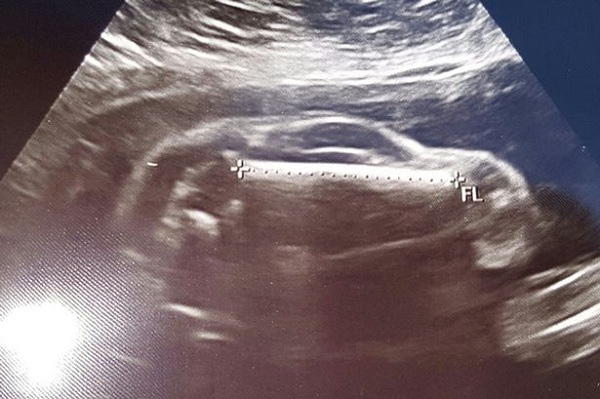

Một cặp vợ chồng đã vô cùng ngạc nhiên khi nhìn thấy trong ảnh siêu âm thai nhi không phải là một em bé mà là một chiếc ô tô thể thao.

Chiếc ô tô xuất hiện trong hình ảnh siêu âm thai nhi.

Mới đây, một người dùng Reddit đã đăng tải hình ảnh siêu âm của vợ mình lên trang mạng trực tuyến này với dòng chia sẻ: “Vợ tôi mang thai một ‘chiếc xe ô tô thể thao’“.

Thông tin về anh chàng sắp làm bố này và vợ của anh ta vẫn chưa được tiết lộ, chỉ biết tên người dùng của anh chàng này trên Reddit là Brewhaus3223. Sau khi đăng tải bức hình lên Reddit, một ngày Brewhaus3223 nhận được rất nhiều lượt chia sẻ và phải trả lời các bình luận liên tục.

Hầu hết mọi người đều đồng ý rằng cậu bé chưa chào đời của vợ chồng anh chàng này có hình dạng giống hệt một chiếc xe ô tô. Nhiều người đã tỏ ra vô cùng thích thú với bức ảnh siêu âm của hai vợ chồng.

Một người đã bình luận hóm hỉnh: “Nếu đó là một cậu bé thì tôi nghĩ anh nên đặt tên cho nó là Chevy”.

Brewhaus3223 cho biết anh và vợ đã cố gắng để có con trong khoảng thời gian 2 năm. Sau nỗ lực và cố gắng thụ tinh trong ống nghiệm, cả hai vợ chồng vui mừng vì cuối cùng người vợ đã mang thai một bé gái.

Sau khi sinh bé gái được 6 tháng thì vợ anh lại mang thai tự nhiên và cái thai lần này có hình ảnh khác thường khiến hai vợ chồng rất ngạc nhiên. Brewhaus3223 tiết lộ rằng lần mang thai này là một cậu bé.